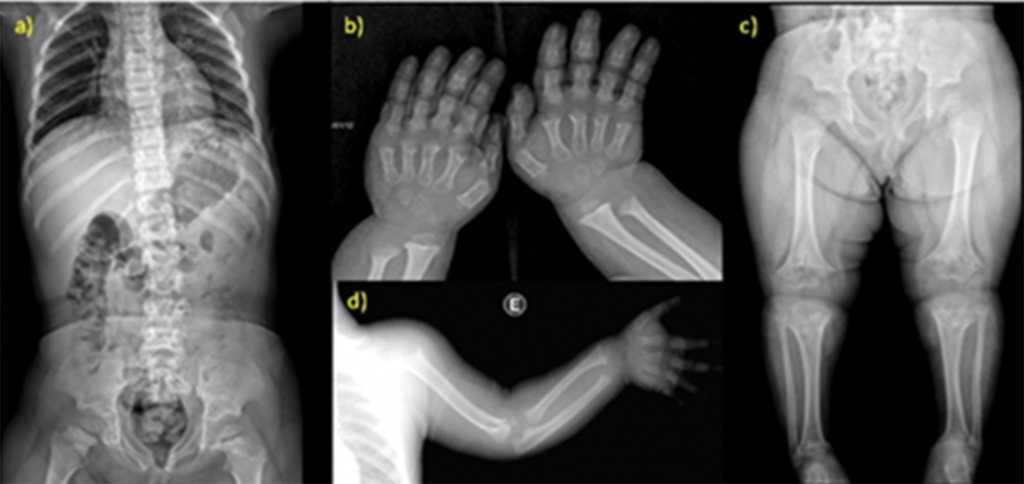

У больных ахондроплазией аномально низкий рост, укороченные конечности, непропорциональный размер туловища. У многих людей наблюдается деформация в грудном отделе позвоночника, поражение коленных суставов. Пальцы на руках могут иметь одинаковую длину.

В большинстве случаев врачи-диагносты правильно определяют патологию на скрининге во время беременности. Первые изменения заметны на 15-16-й неделях, определяются при замере длинных костей эмбриона.

У пациентов с ахондроплазией возникают следующие симптомы и осложнения:

Расширение желудочков головного мозга. Провоцирует повышение внутричерепного давления, частые приступы мигрени, нарушение координации движений. В редких случаях ребенок рождается с гидроцефалией.

Стеноз позвоночного канала и компрессия. Связаны с аномальным строением позвонков в шейном отделе, укорочением дуг, патологическим кифозом позвоночного канала. Нередко осложняются развитием миелопатии.

Большое затылочное отверстие имеет слишком маленький размер. Оно давит на позвоночный канал в шейном отделе. В подростковом возрасте наблюдаются сильные боли и приступы, нарушение походки, снижение чувствительности в конечностях, потеря контроля над выделительной функцией.

Наблюдается поражение черепных нервов. Каналы, через которые проходят окончания у основания черепа, могут страдать от стеноза, сдавливаются при неправильном строении. Это приводит к патологиям слуха, зрения, слабости дыхательных мышц. В сложных случаях у пациента наблюдаются проблемы с глотанием.

При ахондроплазии повышается риск синдрома внезапной смерти во сне. Врачи связывают особенность со сдавливанием продолговатого мозга костью затылочного отверстия. Младенцы часто страдают от нарушения дыхания на фоне неправильного строения передней части черепа, увеличенных миндалин, недоразвитой грудной клетки.